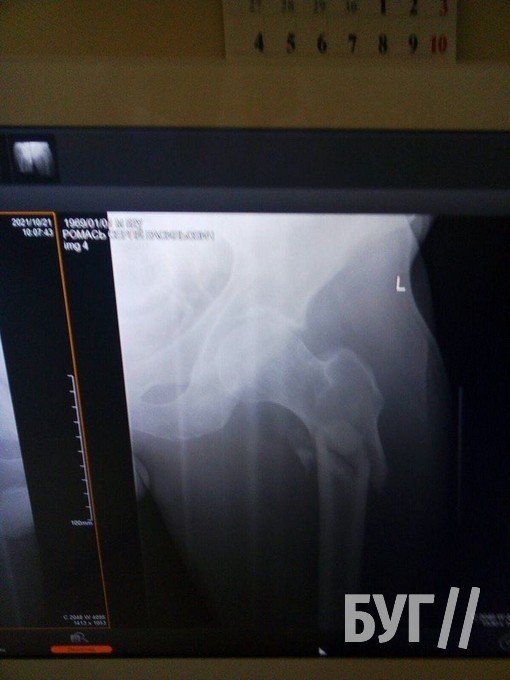

Колишній шахтар Сергій Ромась 20 жовтня отримав травму і потребує заміни суглоба і проведення операції.

У 52-річного чоловіка, який проживає у селі Суходоли, два переломи стегнових кісток і розтрощений кульшовий суглоб, пише БУГ.